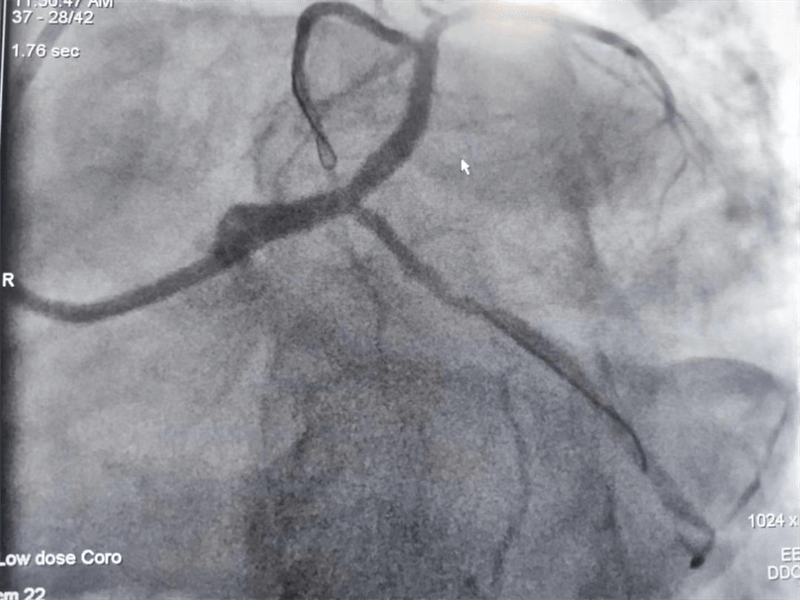

冠脈造影結果提示:左主干末端及前降支開口處99%狹窄,回旋支開口處80-90%狹窄,中段支架內100%閉塞。看到造影結果時,在場醫護人員無不驚出一身冷汗:左主干病變“細”如發絲——生死一線牽!患者拒絕搭橋手術,所以選擇介入處理該病變。

患者在冠脈造影檢查術中,感到胸悶、胸痛發作,血壓下降、心率減慢,我們立即對左主干狹窄段進行球囊擴張后癥狀好轉,生命體征逐漸平穩。